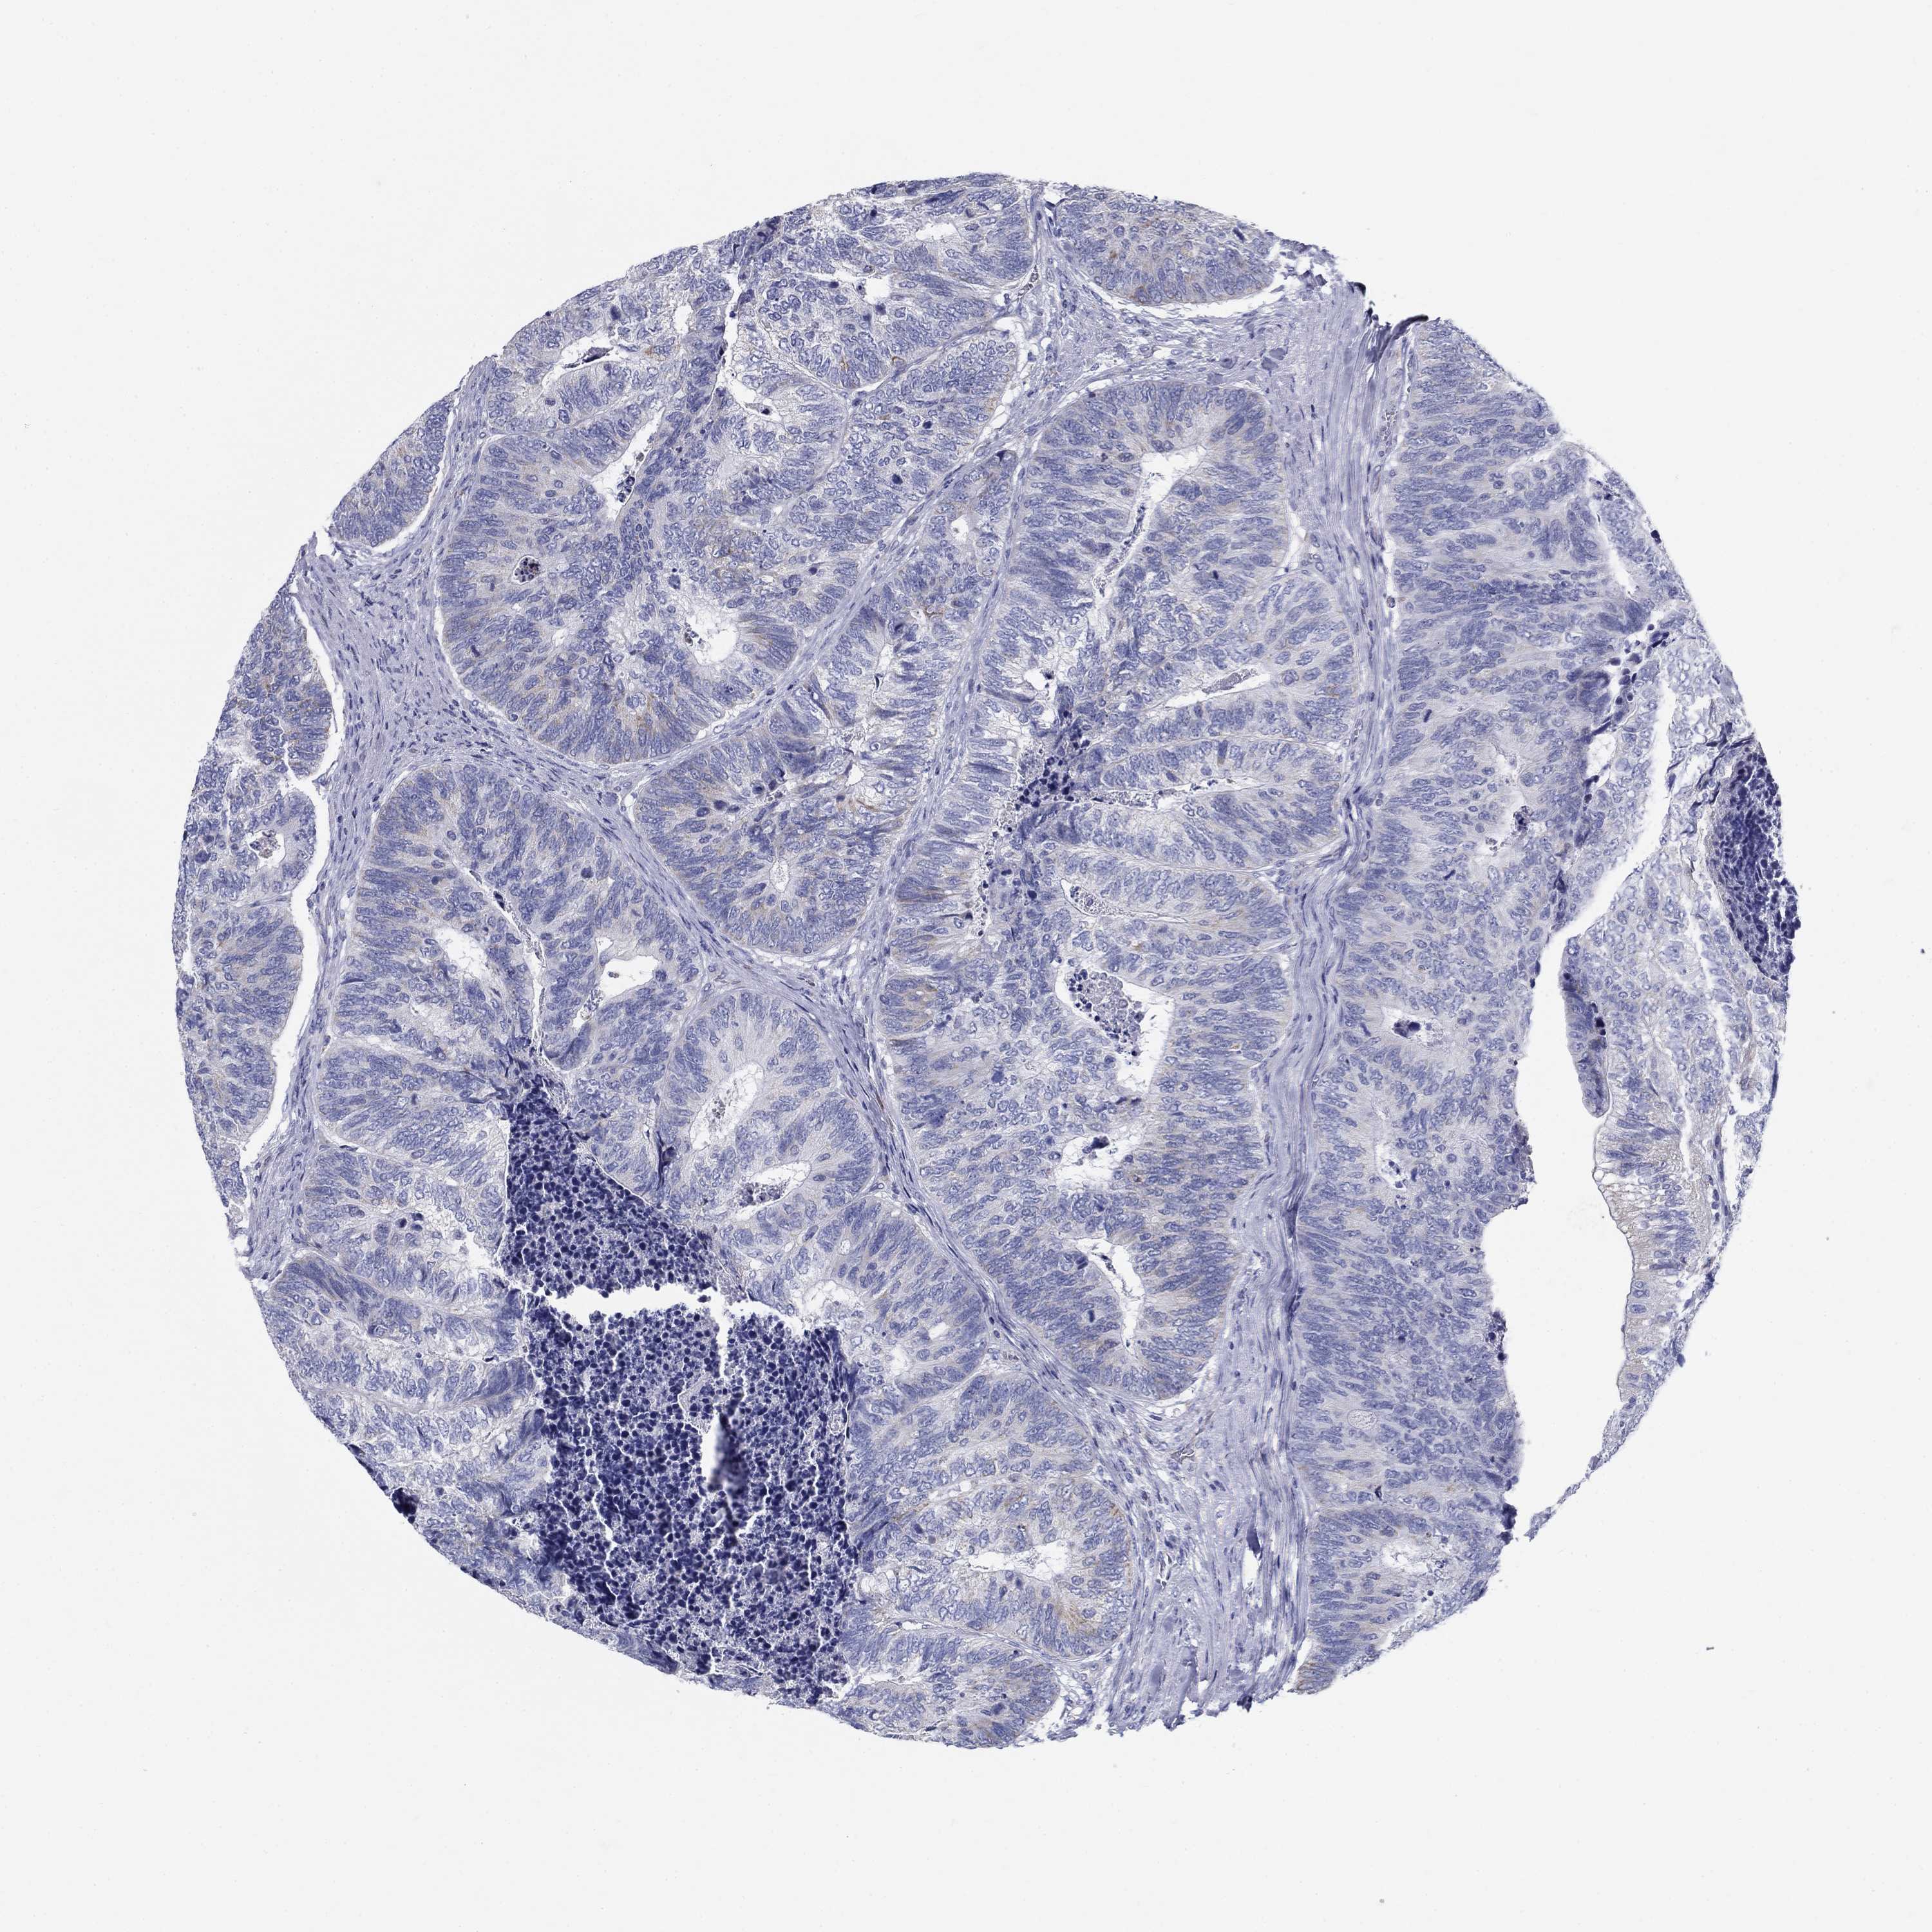

CANCER COLORECTAL CANCER Show tissue menu

ANTIBODIES

AND

VALIDATION

Colorectal cancer

Human cancer

Colon adenocarcinoma